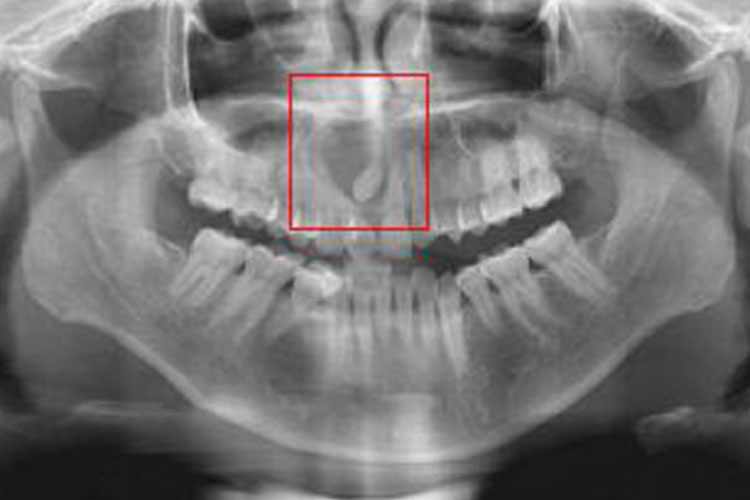

4、牙源性腺样瘤:早期一般无自觉症状,常在颌骨病变区出现无痛性的膨隆,X线表现为单房性境界清楚的透光区,其中可见不透光的斑点,常伴有埋伏牙。好发于上颌尖牙区,好发于10~19岁,女性比男性多见。